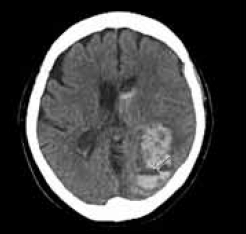

Paciente de 30 anos, previamente saudável, apresenta-se com um quadro clínico de duas semanas de evolução caracterizado por cefaleia persistente, febre baixa e rigidez nucal. O exame do líquido cefalorraquidiano (LCR) revela pleocitose linfocítica, hipoglicorraquia e hiperproteinorraquia.

A tomografia computadorizada (TC) do crânio encontra-se a seguir.

Das seguintes etiologias, a mais provável para os achados clínicos e laboratoriais nesse paciente é: